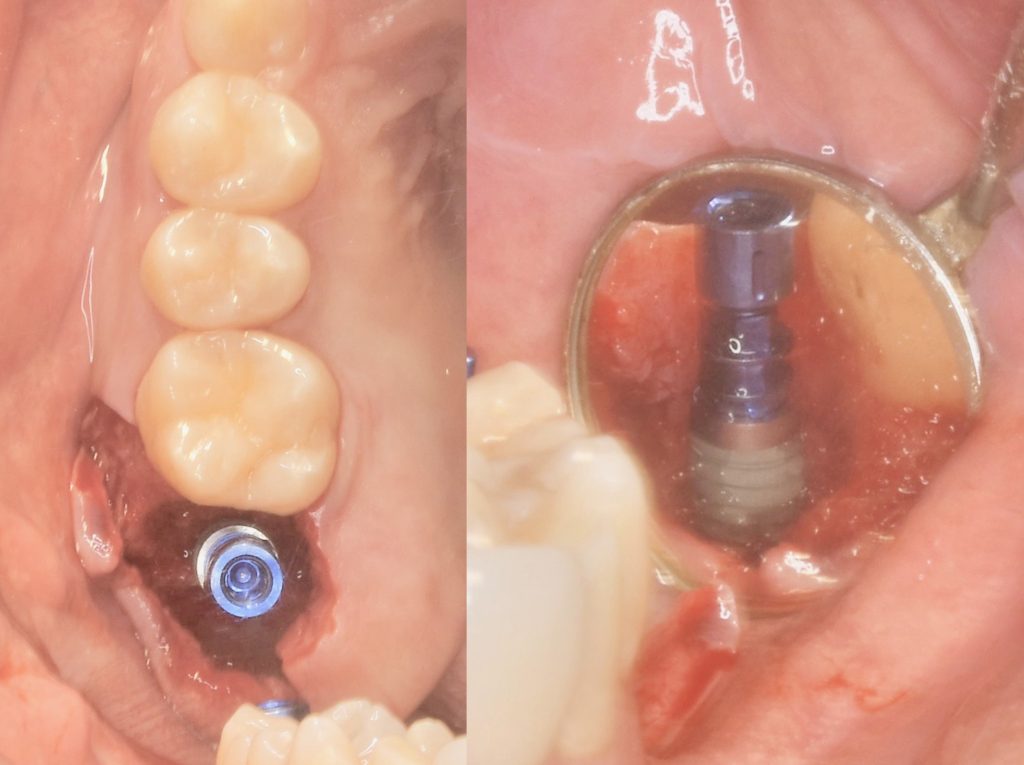

下記の症例は新しくローンチされるインプラントを前もって使用感を確認する為に、適したケースに使わせていただいております。

今回のケースは新しいインプラントを使うことで、骨造成の負担を減らし、清掃性を高める事ができました。